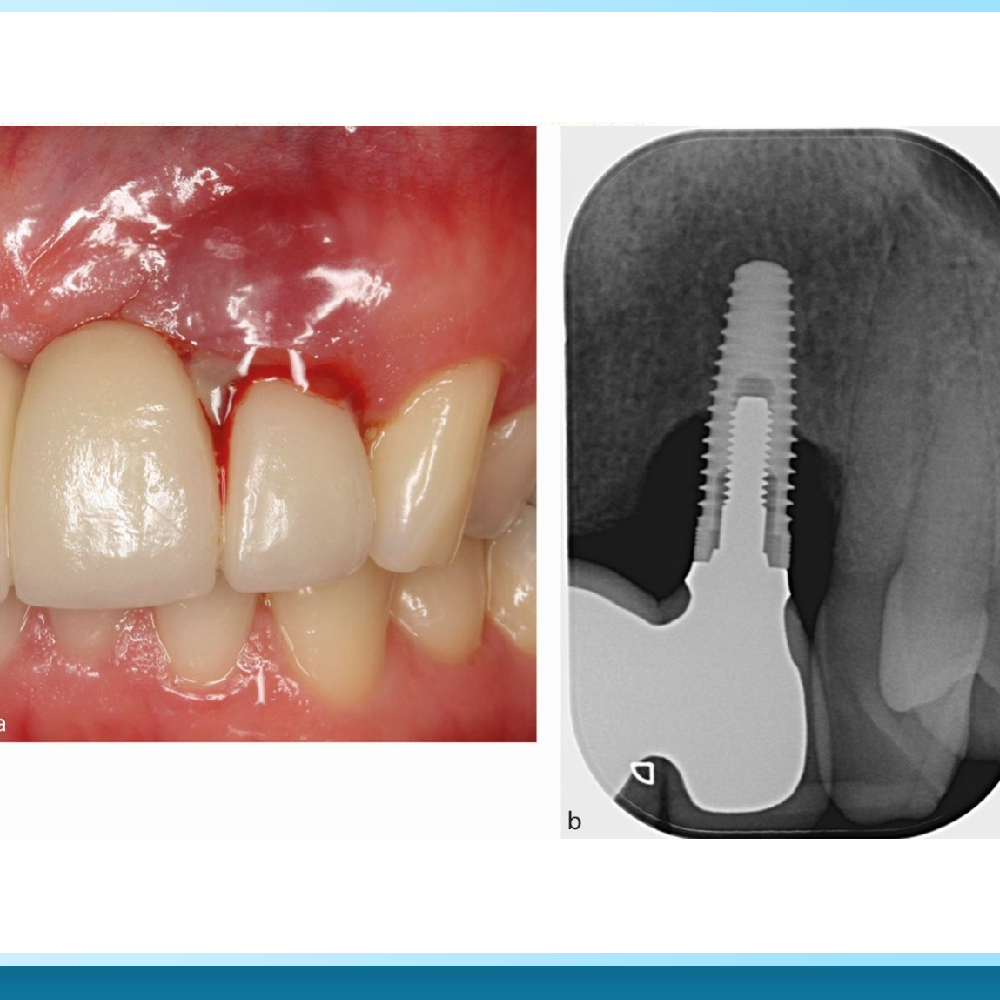

Đây là dấu hiệu phổ biến nhất. Nướu xung quanh trụ Implant sưng đỏ, căng bóng và chuyển sang màu đỏ sẫm thay vì màu hồng hào khỏe mạnh. Khi ấn nhẹ vào vùng nướu này, bạn có thể thấy chảy mủ và cảm nhận mùi hôi khó chịu trong miệng dù đã vệ sinh kỹ.

2. Lộ thân trụ Implant

Trong một số trường hợp, do nướu bị tụt hoặc xương quanh cổ Implant bị tiêu đi quá nhanh, bạn có thể nhìn thấy rõ các vòng ren xoắn kim loại của trụ Implant hoặc phần chốt Abutment bị lộ ra ngoài. Điều này không chỉ gây mất thẩm mỹ mà còn tạo điều kiện cho vi khuẩn tấn công sâu xuống dưới.